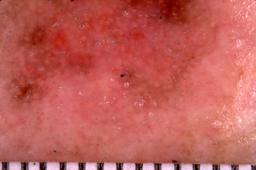

{

"age_approx": 70,

"anatom_site_general": "head/neck",

"concomitant_biopsy": true,

"dermoscopic_type": "contact non-polarized",

"diagnosis_1": "Indeterminate",

"diagnosis_2": "Indeterminate epidermal proliferations",

"diagnosis_3": "Solar or actinic keratosis",

"diagnosis_4": "Actinic keratosis, Lichenoid",

"diagnosis_confirm_type": "histopathology",

"image_type": "dermoscopic",

"lesion_id": "IL_5320579",

"patient_id": "IP_4936244",

"sex": "male"